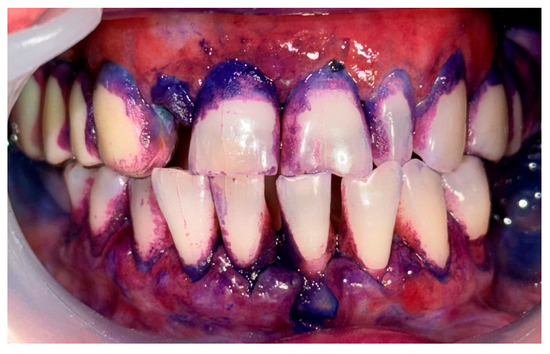

2.1. Clinical Case 1—Mucous Membrane Pemphigoid (MMP)